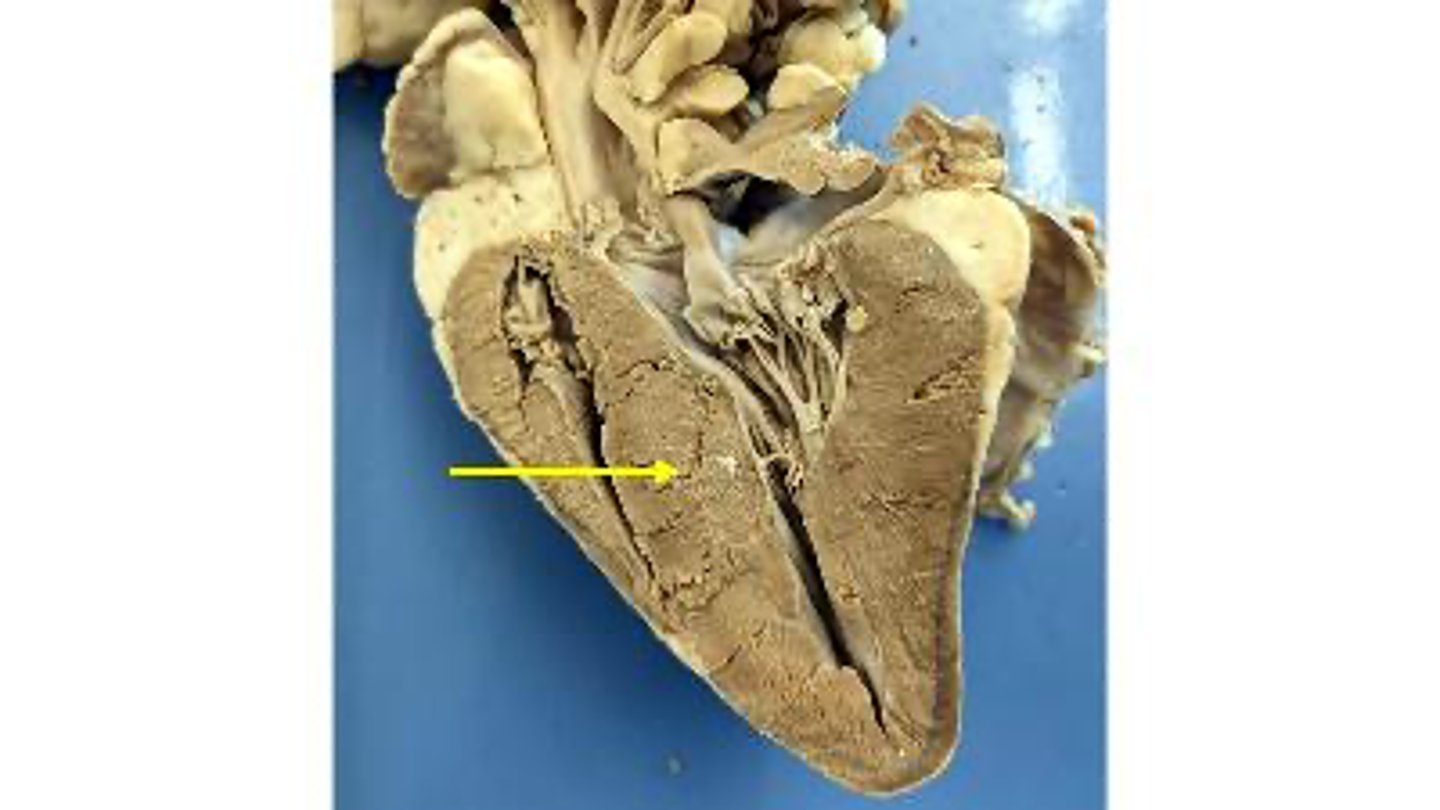

Right ventricle

what is this

Papillary muscle

Interventricular septum

Left ventricle